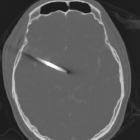

High-velocity penetrating brain injury

As is the case with low-velocity penetrating brain injuries, CT and CT angiography are the cornerstones of emergent imaging of all patients with penetrating injuries. Plain films have largely been replaced by CT and MRI is usually not indicated until later in the admission if at all. Of particular importance is the possibility that the penetrating material is ferromagnetic precluding safe MRI.

A number of features need to be assessed in patients with penetrating injuries, with care taken to carefully document findings as often these scans will be used in medicolegal proceedings.

Foreign bodies

Location, number (sometimes difficult if highly fragmented) and density (usually metal in high-velocity injuries) of fragments, particularly in relation to eloquent parts of the brain or vessels.

Parenchyma and hematomas

The direction of tract(s) and the key structures they traverse along with the amount of hemorrhage, particularly if there are sizable hematomas that need evacuation. This is particularly the case for extra-axial hemorrhages that may occur due to vascular injury.